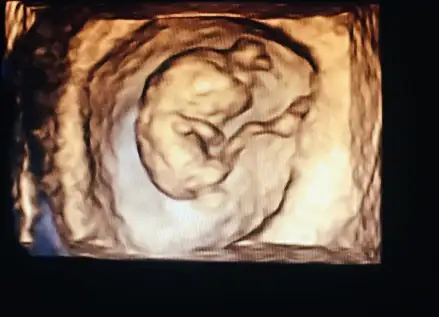

Eklentiler

• 128FCCFE-01AA-48FB-9FA1-B4E3AC112934.webp

18 KB · Görüntüleme: 55

• 0F1986DE-AAAA-4A94-92AB-7FABD4ED0483.webp

22,9 KB · Görüntüleme: 45

• FEE9F5B9-A014-4C8E-A6C4-3BB4B84EA231.webp

25,3 KB · Görüntüleme: 53